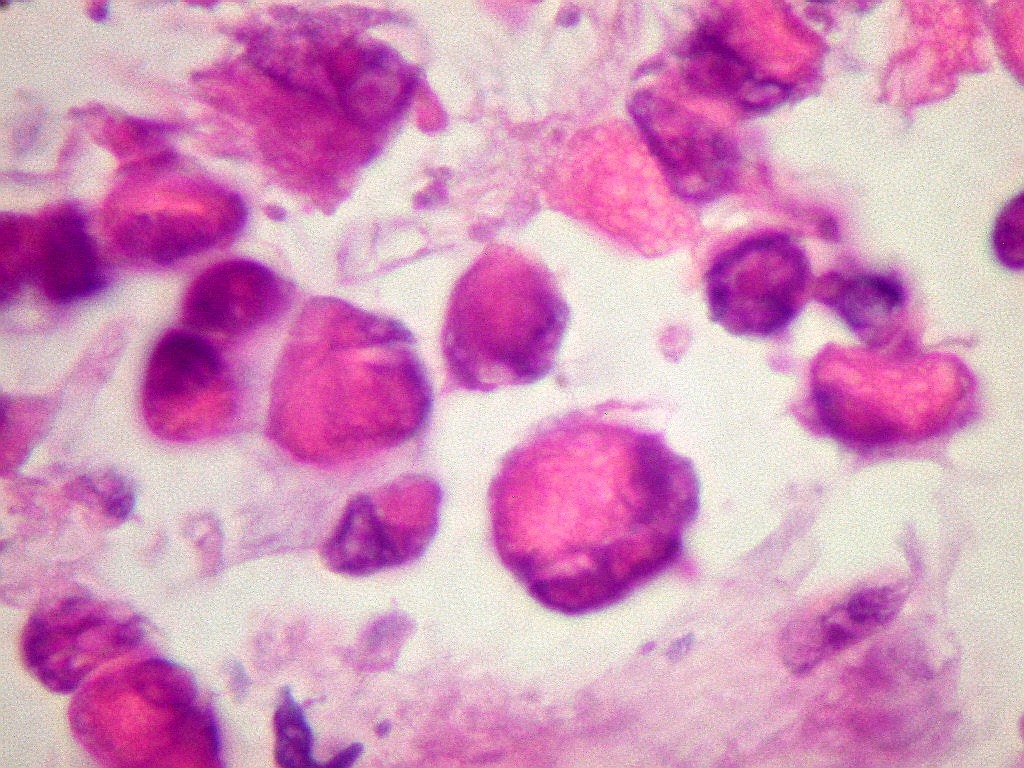

INI1.

Antígeno nuclear presente em todas as células normais.

Sua ausência é importante marcador do tumor teratóide

rabdóide atípico (metade direita do campo). Na metade

esquerda, vaso com células positivas. Os vasos não

pertencem ao tumor, mas o invadem a partir dos tecidos infiltrados. |

| INI1.

Células neoplásicas negativas (centro) e epêndima positivo

(em cima) (não neoplásico) |

Células vasculares INI1 positivas, células neoplásicas

negativas (embaixo) |

INI1. Linfócitos

positivos. Como células inflamatórias, não pertencem

ao tumor. |